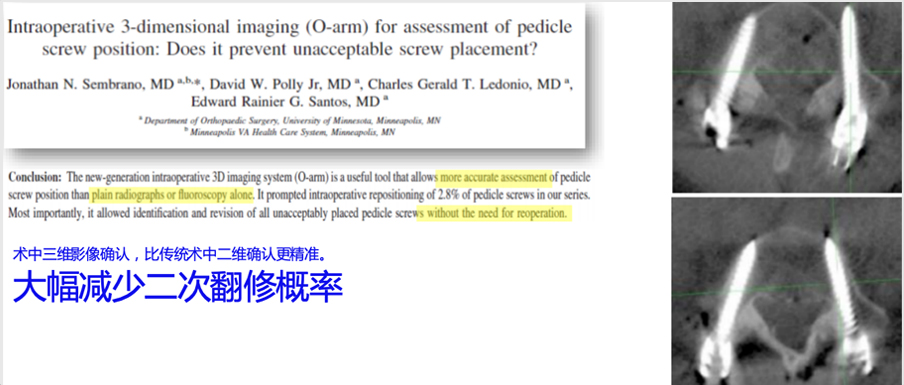

三維影像能大幅提高導航可視化與手術計劃的精準度

全型號三維影像自動配準

10秒內自動配準

配準算法精度可達0.19mm